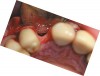

A full mucoperiosteal flap was reflected (Figure 1), and the residual roots of the two damaged teeth were extracted atraumatically, preserving the residual alveolar housing (Figure 2). Although thin, the facial plate was maintained to act as a supportive structure for the grafting material and membrane.

Figure 1  Full-thickness flap reflection exposed the left lateral incisor, which was fractured and intruded apically beyond the alveolar housing.

Figure 1